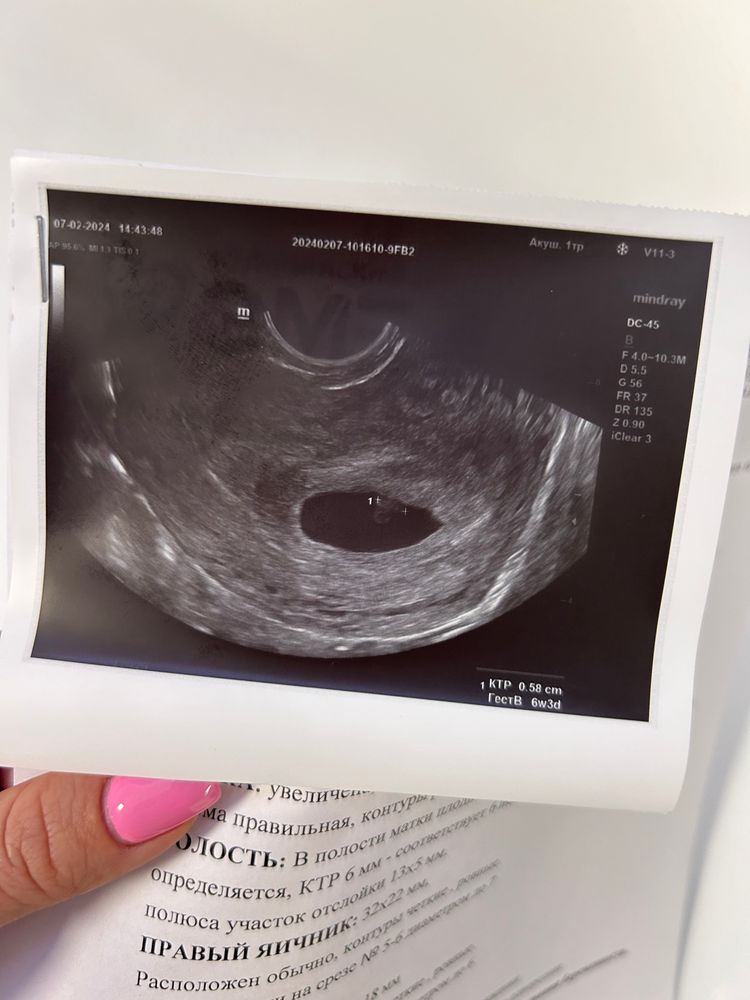

7 недель по М-отслойка

Ехала ночью в поезде, почувствовала тянущую боль внизу живота, пошла в туалет и увидела кровь, не алая, не текла, просто мазало

приехала и сразу пошла на узи и к врачу🥺 выписали пока что дюфастон 3 раза в день до понедельника и там уже узи контрольное